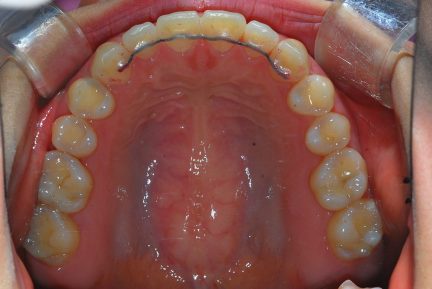

État final

- Arcades alignées et coordonnées

- Arcades harmonieuses obtenues

- Maxillaire : Fixe/Collé

Surtout après la fermeture d'espace, le contrôle de l'inclinaison linguale buccale des dents antérieures inférieures était excellent.